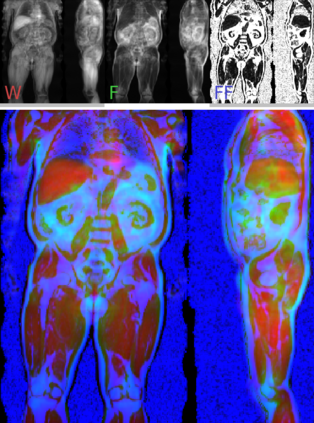

Along with rich health-related metadata, an ongoing imaging study has acquired MRI of over 40,000 male and female UK Biobank participants aged 44-82 since 2014. Phenotypes derived from these images, such as measurements of body composition, can reveal new links between genetics, cardiovascular disease, and metabolic conditions. In this retrospective study, six measurements of body composition were automatically estimated by ResNet50 neural networks for image-based regression from neck-to-knee body MRI. Despite the potential for high speed and accuracy, these networks produce no output segmentations that could indicate the reliability of individual measurements. The presented experiments therefore examine mean-variance regression and ensembling for predictive uncertainty estimation, which can quantify individual measurement errors and thereby help to identify potential outliers, anomalies, and other failure cases automatically. In 10-fold cross-validation on data of about 8,500 subjects, mean-variance regression and ensembling showed complementary benefits, reducing the mean absolute error across all predictions by 12%. Both improved the calibration of uncertainties and their ability to identify high prediction errors. With intra-class correlation coefficients (ICC) above 0.97, all targets except the liver fat content yielded relative measurement errors below 5%. Testing on another 1,000 subjects showed consistent performance, and the method was finally deployed for inference to 30,000 subjects with missing reference values. The results indicate that deep regression ensembles could ultimately provide automated, uncertainty-aware measurements of body composition for more than 120,000 UK Biobank neck-to-knee body MRI that are to be acquired within the coming years.